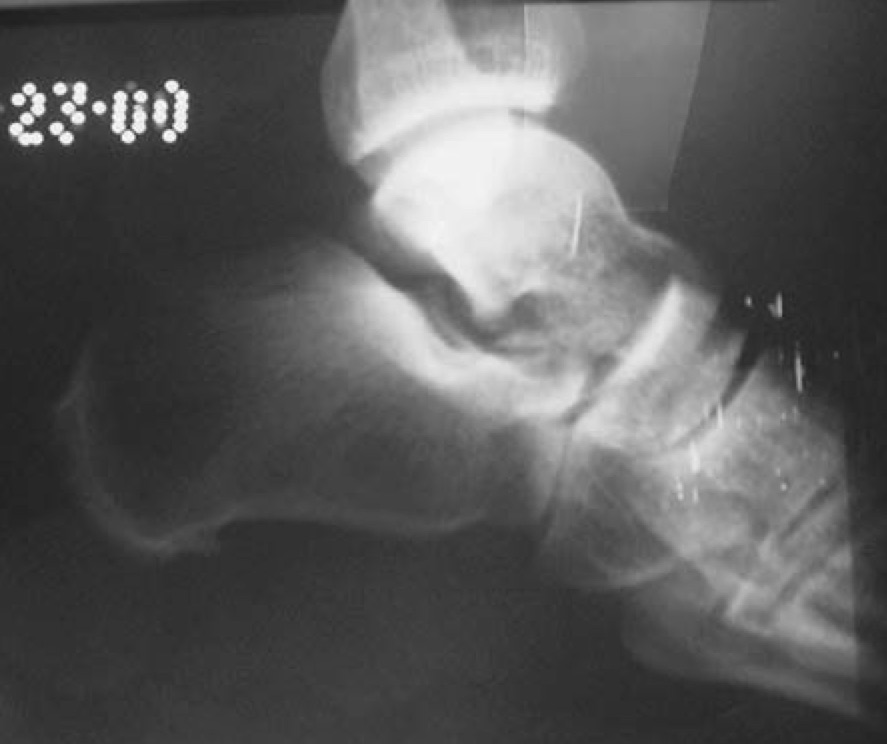

- Radiographs

- medial dislocation

- talar head will be superior to navicular on lateral view

- lateral dislocation

- talar head will be collinear or inferior to navicular on lateral view